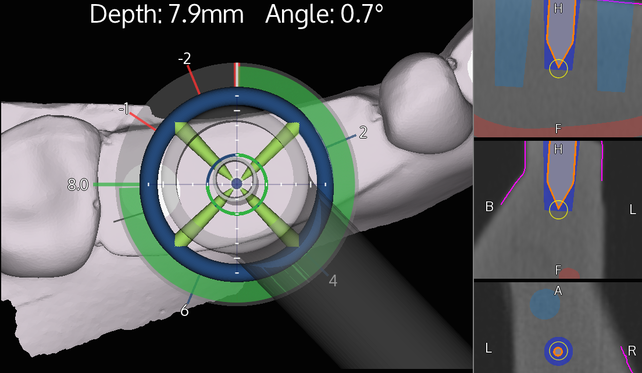

Browse our specialized Calibration In Dynamic Navigation Surgery In Implamt portfolio with numerous expertly curated photographs. optimized for both digital and print applications across multiple platforms. providing reliable visual resources for business and academic use. Each Calibration In Dynamic Navigation Surgery In Implamt image is carefully selected for superior visual impact and professional quality. Perfect for marketing materials, corporate presentations, advertising campaigns, and professional publications All Calibration In Dynamic Navigation Surgery In Implamt images are available in high resolution with professional-grade quality, optimized for both digital and print applications, and include comprehensive metadata for easy organization and usage. Our Calibration In Dynamic Navigation Surgery In Implamt collection provides reliable visual resources for business presentations and marketing materials. Whether for commercial projects or personal use, our Calibration In Dynamic Navigation Surgery In Implamt collection delivers consistent excellence. The Calibration In Dynamic Navigation Surgery In Implamt archive serves professionals, educators, and creatives across diverse industries. Regular updates keep the Calibration In Dynamic Navigation Surgery In Implamt collection current with contemporary trends and styles. Advanced search capabilities make finding the perfect Calibration In Dynamic Navigation Surgery In Implamt image effortless and efficient. Multiple resolution options ensure optimal performance across different platforms and applications.